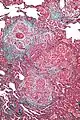

High magnification photomicrograph of a lung biopsy taken showing chronic hypersensitivity pneumonitis (H&E), showing mild thickening of the walls of the small air sacs by invasion of white blood cells. A multinucleated giant cell, seen within the walls of the air sacs to the right of the picture halfway down, is an important clue to the correct diagnosis.

Low magnification view of the histology of chronic hypersensitivity pneumonitis. The interstitium is expanded by a chronic inflammatory infiltrate. Two multinucleated giant cells can be seen within the interstitium at left, and a plug of organizing pneumonia at bottom left.

Lung biopsies can be diagnostic in cases of chronic hypersensitivity pneumonitis, or may help to suggest the diagnosis and trigger or intensify the search for an allergen. The main feature of chronic hypersensitivity pneumonitis on lung biopsies is expansion of the interstitium by lymphocytes accompanied by an occasional multinucleated giant cell or loose granuloma.[7][22]

When fibrosis develops in chronic hypersensitivity pneumonitis, the differential diagnosis in lung biopsies includes the idiopathic interstitial pneumonias.[23] This group of diseases includes usual interstitial pneumonia, non-specific interstitial pneumonia and cryptogenic organizing pneumonia, among others.[7][22]